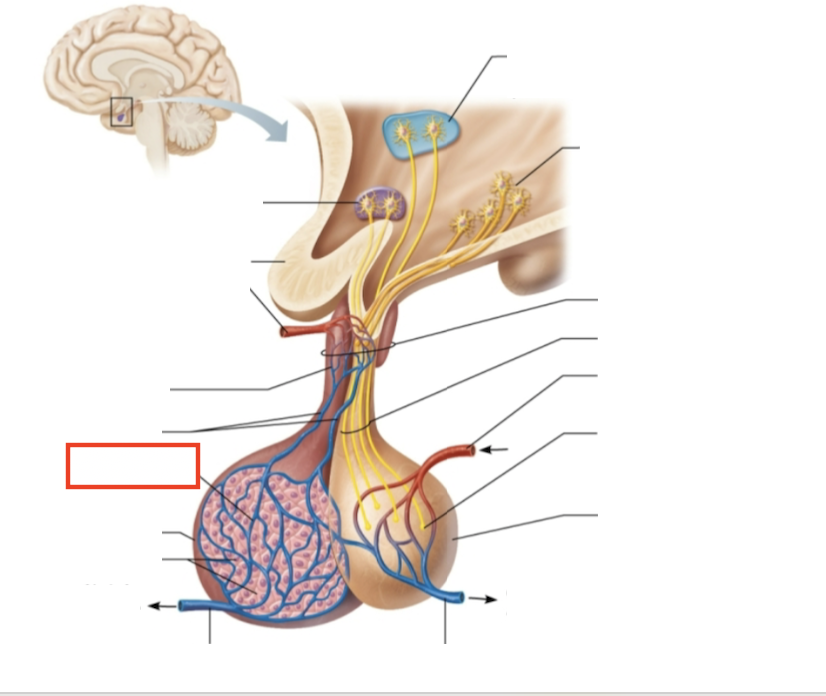

What structure is highlighted?

testes (male)

What are the target organs and effects of testosterone?

most cells of the body; promotes the maturation of the male reproductive organs, the development of secondary sex characteristics, sperm production, and sex drive

What hormone is produced by the testes?

testosterone

What stimulates testosterone production?

LH and FSH